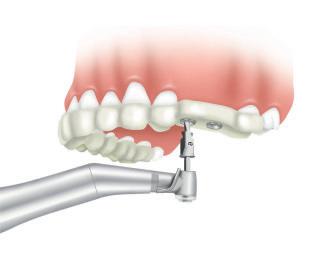

1. Adaptable to different guided surgery protocols: piloted, semi-guided or fully guided.

2. No friction between drills and guide sleeve, no overheating and no release of particles.

3. No specific drills and a very small surgical box.

4. Full control of drilling depth.

5. Your conventional driver-guided drilling sequence.